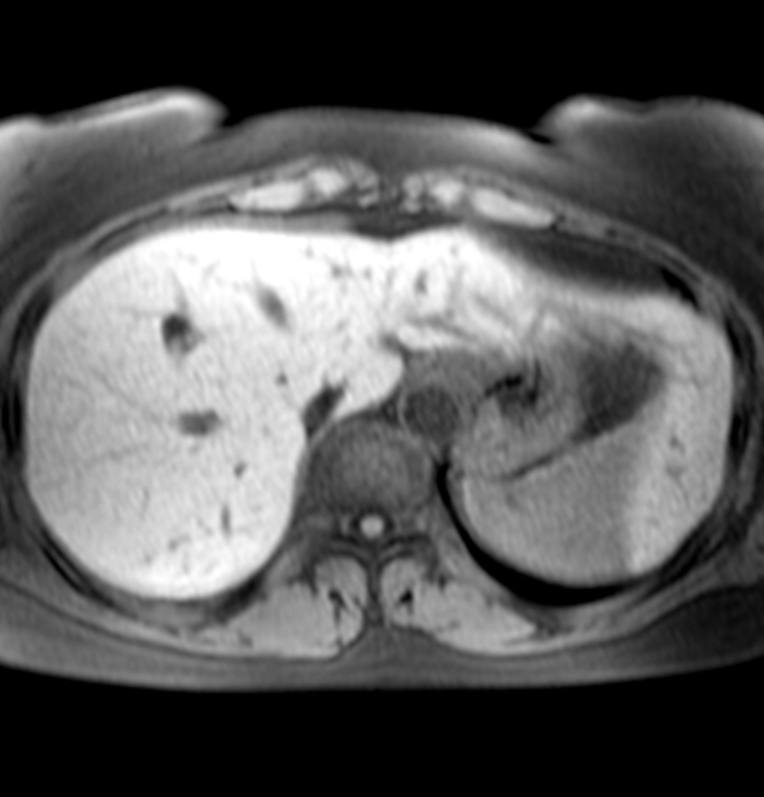

40 лет.

Думаю, что рак в хвосте панкреас, с вот такими метастазами в печень.

Ну, или и в панкреас тоже метастаз, хотя, других опухолей в животе не обнаруживается.